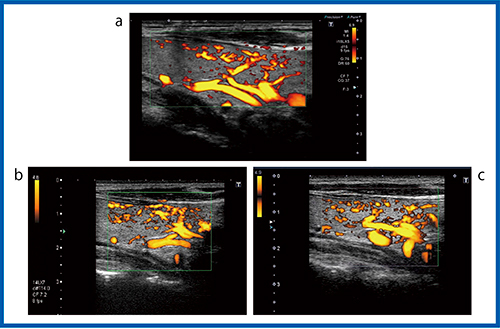

より低速な血流を描出できるSMIでは,装置の性能が向上することで血管の描出能の違いがより明確にわかる。図8は,color-coded SMI(cSMI)でカラー表示された血流の画像だが,Aplio i800(b)では通常の血流に加えて,腫瘍の内部まで入り込むような微細な血管の様子まで確認することができる。また,血流信号をモノクロで表示したmonochrome SMI(mSMI,図9)の場合,Aplio i800(b)では濾胞構造を示す腫瘍の周囲の血管構造まで確認できるほど低流速の血流が描出されている。

濾胞性腫瘍の血管構築は,良性では類円形の血管走行できれいな濾胞を描いているが,癌腫ではイレギュラーに網目状に発達した構造を示す。癌腫は進行するにしたがって主要血管網の中心を貫通する血管が認められ,カラードプラにて悪性を疑う濾胞内部の拍動性の血流と類似する。図9 bのAplio i800のmSMIの画像は,甲状腺濾胞の周囲を囲む類円形状の血流を描出しているとも考えられる。さらに高精細な血流の描出が可能になれば,SMIによって癌腫の複雑な網目状の血管構造が描出できることが期待される(図10)。

図10 SMIによる濾胞性腫瘍の描出

a:共焦点レーザー顕微鏡像* b:mSMI

(*伊藤病院・佐々木栄司氏提供)